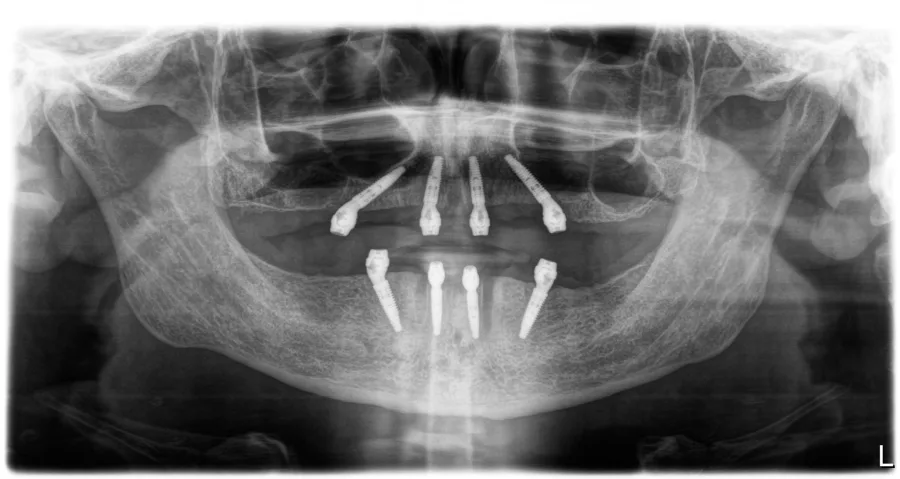

2. Hirurški Zahvat: Iskusni kirurzi izvode precizan postupak ugrađivanja implantata u čeljust.

3. Oporavak i Integracija: Period oporavka omogućuje implantatima da se čvrsto integriraju s kostima čeljusti, stvarajući trajnu stabilnost.